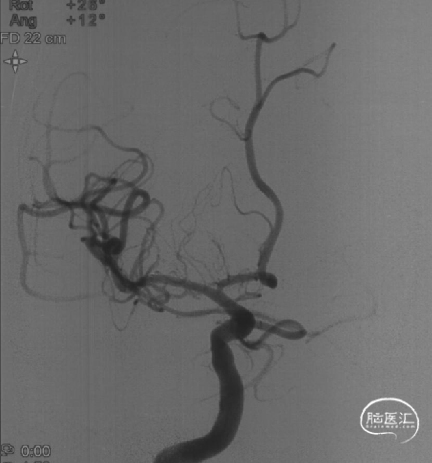

➤术前DSA检查

右侧大脑中动脉重度狭窄,左侧前循环未见明显异常。

后循环未见明显异常。

病变部位: 右侧大脑中动脉M1段重度狭窄;狭窄率: 75.6%;狭窄长度: 6.10mm;参考远端血管直径: 1.27mm。

6F Envoy DA导引导管到位,Synchro2微导丝通过病变。

选用1.5-9mm 颅内球囊扩张导管通过病变。

10atm扩张90s。

泄球囊后可见狭窄明显改善。

选用赛诺神畅 3.5-20mm COMETIU™自膨式颅内药物涂层支架系统通过病变并缓慢释放,释放后造影,支架定位准确,完全覆盖病变,成形效果好。

撤出导管导丝后造影,可见靶血管支架贴壁良好,前向血流通畅稳定。

2022-07-27 术前正位

2022-07-27 术前侧位